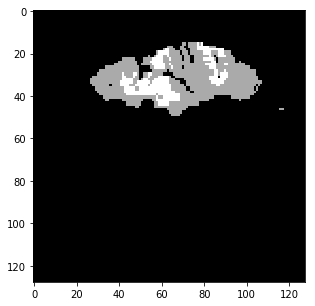

The qualitative results are shown in Fig. 2. Addition of LS and BD losses while training the network significantly improves the boundary delineation in the results. This improvement is more drastic when the network is adversarially trained as seen in the results of the proposed method as compared to BL7.

[TMax]

\subfigure[TTP]

\subfigure[DWI]

\subfigure[GT]

[BL3]

\subfigure[BL4]

\subfigure[BL7]

\subfigure[Proposed]